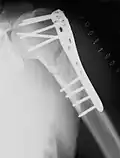

Als extramedulläre Operationsverfahren kommen hauptsächlich Plattenosteosynthesen und der Fixateur externe zur Anwendung. Bei besonderen Bruchformen, insbesondere bei sehr gelenknahen Brüchen, kommen seit den 1990er Jahren auch winkelstabile Platten zum Einsatz.

Eine Ausnahme sind distale und proximale Schaftfrakturen, die aufgrund der Hebelverhältnisse eine sichere Verriegelung eines Nagels nicht zulassen. Im distalen Bereich wird die Plattenosteosynthese daher weiterhin eingesetzt, im proximalen Bereich kommen seit den 1990er Jahren zunehmend winkelstabile Titanplatten zum Einsatz.